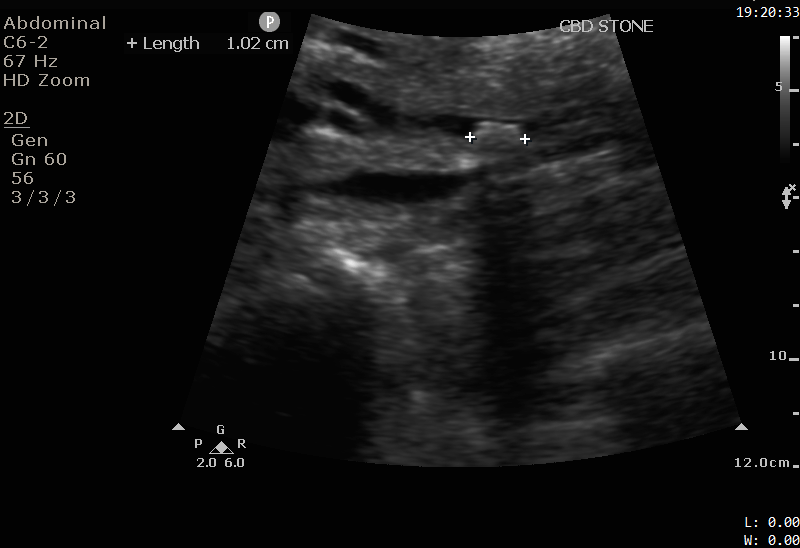

cbd-ls-stone-1